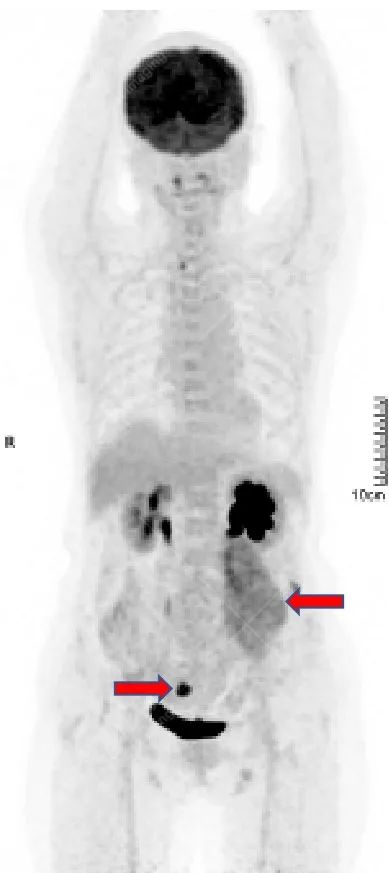

女性,56 岁,腹膜后肿物切除术后 6 月余。术后病理:未分化多形性肉瘤。术后口服靶向药,无放疗、化疗。

现复查提示术区肿瘤复发。

影像所见:左腹膜后间隙(原术区)见一长椭圆形软组织密度肿块影,范围约 8.0 cm×6.6 cm×15.8 cm,CT 值 30 Hu,FDG 高摄取,SUVmax5.0,考虑肿瘤复发,侵犯相邻左侧输尿管、腰大肌、后腹壁。

盆腔内(直肠右旁)见一转移性淋巴结,FDG 高摄取,SUVmax7.7。